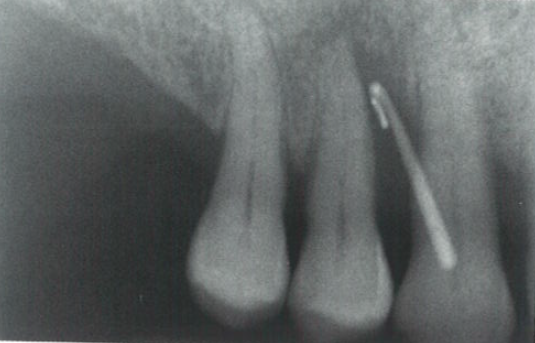

临床情况保持稳定约2年,从最初的治疗开始已经过了大约22年,在第一象限的同一区域发生了第三次复发(图5和图6),在复发期间,瘘管位于颊侧(图7)。根尖片(图8)显示插入光纤所示的瘘管的路径。之所以选择非手术治疗是因为患牙仍有牙髓活力,并且患者只有轻微不适,并无明显疼痛。

图7  颊侧瘘管

图8  根尖片显示插入光纤所示的瘘管的路径